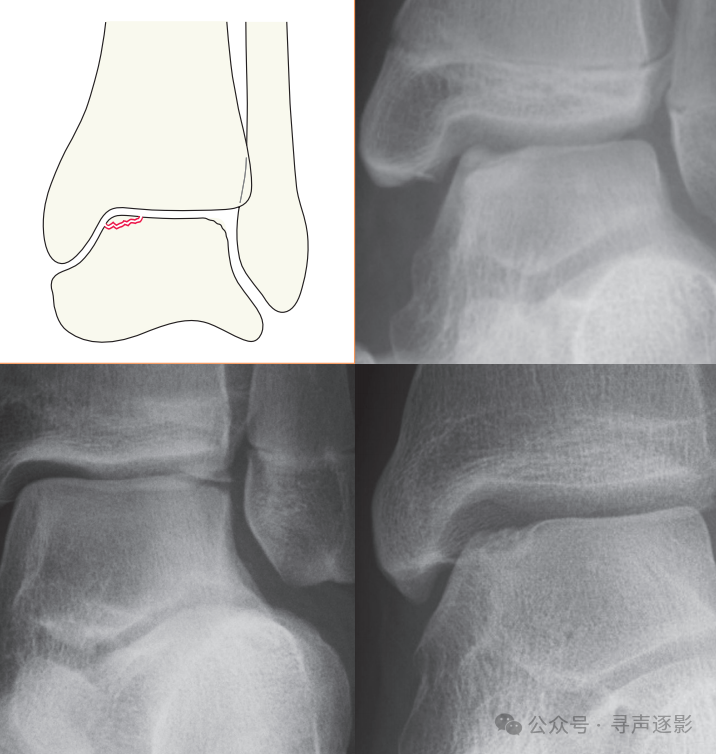

左图:外踝横形骨折。右图:内踝横形骨折;腓骨远端及外踝斜形与横形骨折;距骨外侧半脱位。

左图:胫骨与腓骨多处骨折。右图:注意胫腓关节间隙明显增宽,提示骨间膜断裂。距骨外侧突可见小碎骨片(箭头所示),提示韧带损伤。

在实际工作中,必须将前后位片与侧位片视为一组,一并评估。该患者的前后位片显示外踝横形骨折及距骨外侧半脱位;侧位片则清晰呈现腓骨骨折的全长及移位程度,并可同时评估后踝、距骨及跟骨的情况。